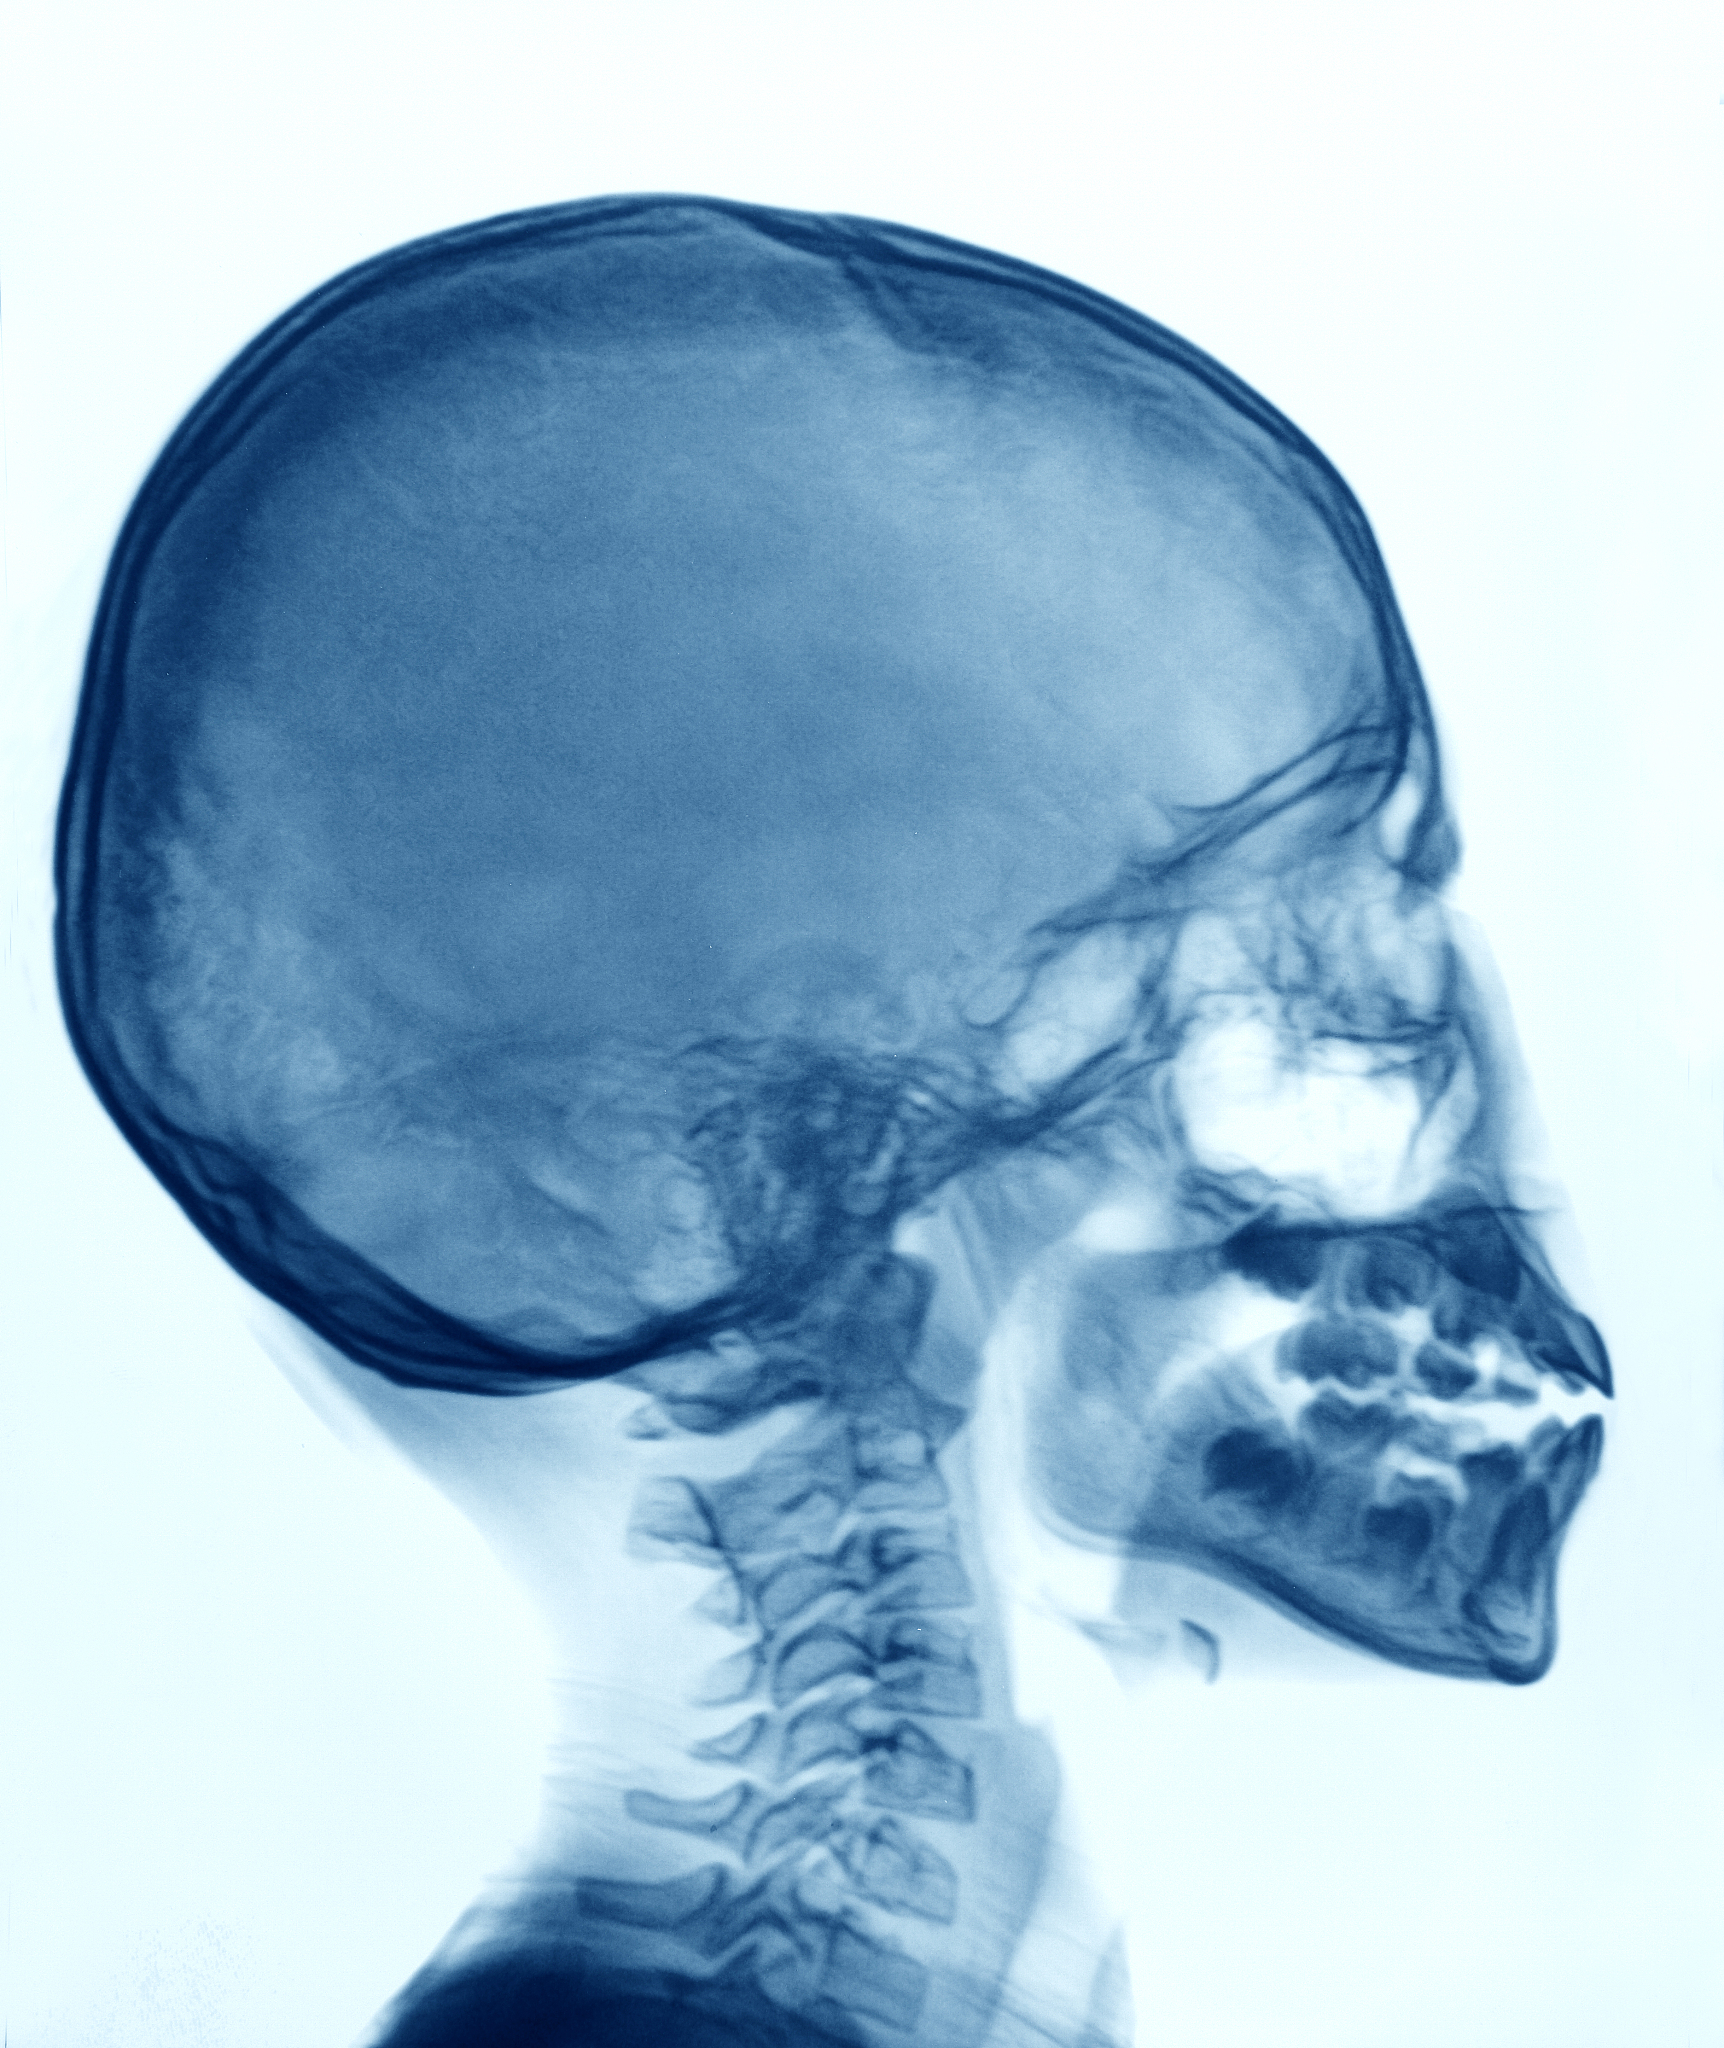

硬脊膜是一种包裹着脊髓和脑的膜,如果它意外穿破,会导致脑脊液的泄漏,引起头痛等症状。这种情况通常是由于创伤、手术或注射等原因造成的。头痛可能是剧烈的、持续的,伴随着恶心、呕吐、颈部僵硬等症状。如果出现这种情况,应及时就医,进行相关检查和治疗。治疗的方式包括休息、补充液体、镇痛、手术等,具体根据病情而定。